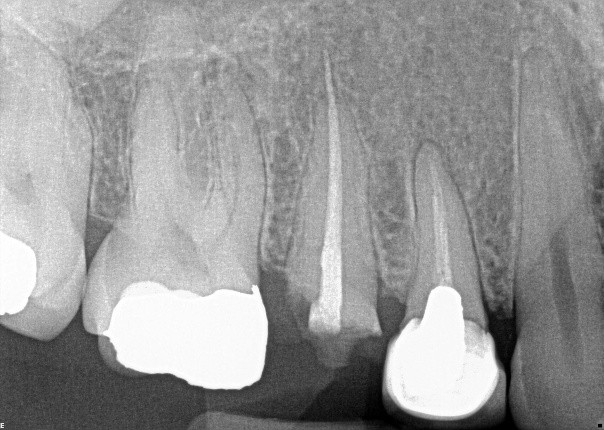

3. (Select ONE OR MORE correct answers)

What observation(s) can be made for tooth 1.5?